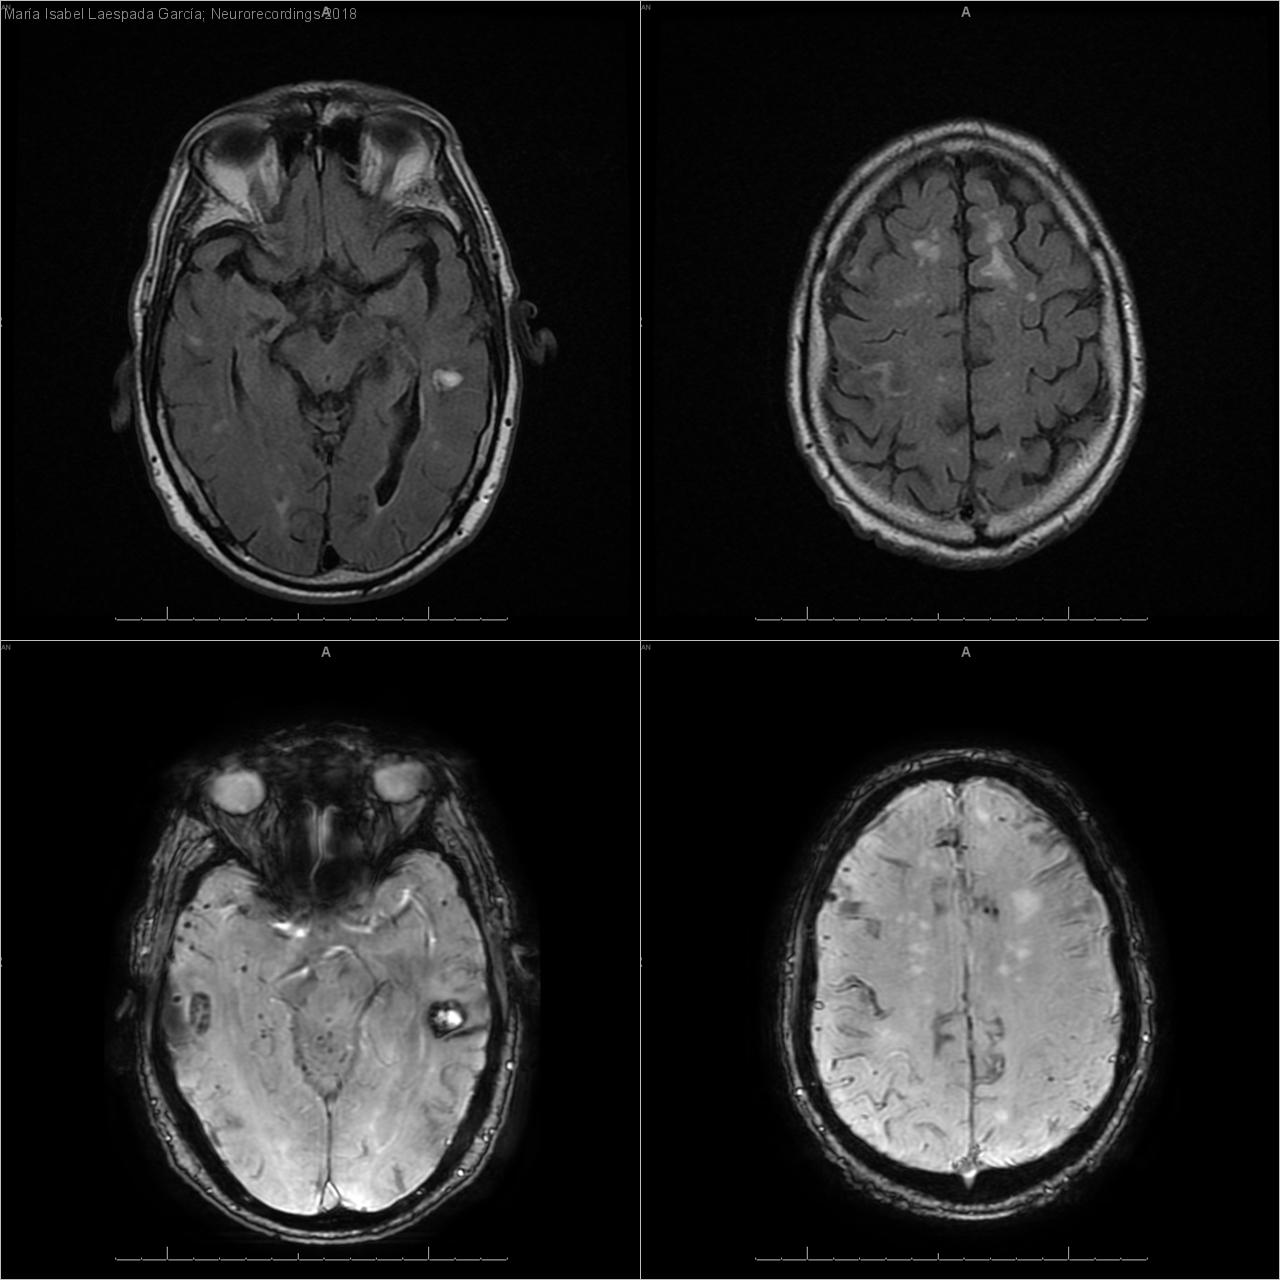

Hombre | 78 años

Diagnóstico final: Angiopatía amiloide cerebral

Neurología: Patología cerebrovascular

Etiología: Ictus

Varón de 78 años con antecedentes de hipertensión arterial en tratamiento farmacológico, glucemia alterada en ayunas, deterioro cognitivo leve de etiología mixta (vascular +/- degenerativa primaria) y episodio de neuralgia del trigémino derecho post-traumática resuelta en...